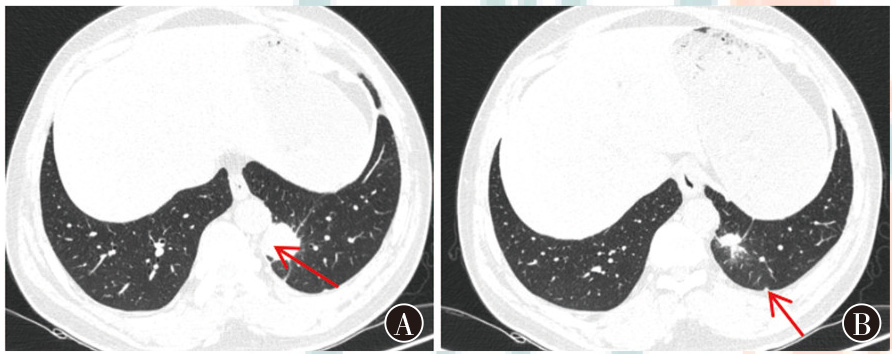

表皮生长因子受体(EGFR)基因L858R突变和棘皮动物微管相关蛋白样4-间变淋巴瘤激酶(ALK)基因融合肺腺癌是一种具有特定分子特征的恶性肿瘤,其恶性程度较高,且对传统治疗手段反应有限。分子靶向治疗是一种精准治疗策略,它通过特定的分子药物针对肿瘤细胞的特定分子靶点发挥作用,从而抑制肿瘤的生长和扩散。现报道1例EGFR基因突变和ALK基因融合肺腺癌的诊疗过程,复习相关文献并讨论,以期为临床提供诊疗思路。